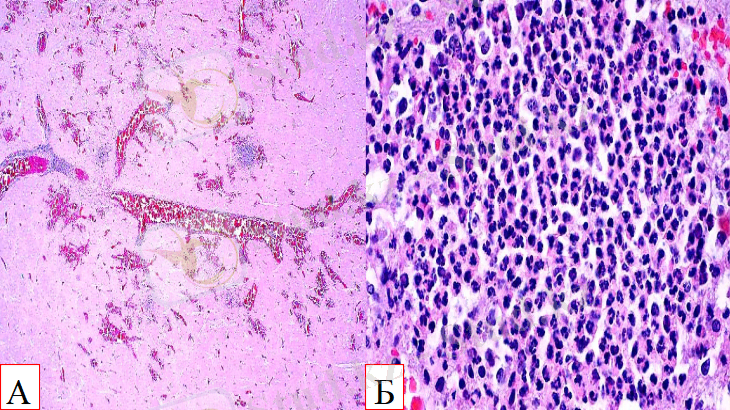

Энцефалит: А. Қозы миы Б. Ірі қара малдың сопақша миы

Мидағы қабыну мына көріністермен сипатталады:

1) Периваскулярлы инфильтрация- қан тамырларын торшалық муфталардың жан-жағынан қоршай орналасуы

2) Инфильтраттардың түзілуі ( торша элементтерінің қан және лимфамен араласып, ұлпада шоғырлануы)

- ошақты және диффузды полиморфты лейкоциттер мен гистиоциттердің инфильтраты;

- моноциттердің инфильтраты;

- лимфоциттермен макрофагтар инфильтраты - ми ұлпасында;

- жеке нейтрофильді лейкоциттер инфильтраты (іріңді инфильтрат) - орталық жүйке жүйесінің талшықтарында;

Бұл инфильтраттар нығызданады, осылайша мүше склерозға ұшырайды, склероз абсцесстің ( іріңді қабыну) пайда болуына әкеледі.

3) Пролиферация ( торшалар бөлініп, көбеюінен ұлпаның өсуі)

- глия элементтерінің өсуі

4) Нейрондар дистрофияға ұшырайды, глиоциттермен қоршалады (нейронофагия)

5) Тамырлардың кеңеюі[4]

Ми талшығы: А. Периваскулярлы инфильтрацияның майда ошақтары. Тамырлар қабынған торшаларға толып және қоршалып тұр.

Б. Нейрофилдерден (сандары әртүрлі макрофаг пен лимфоциттер) тұратын периваскулярлы қабынған торшалар.

Мида лейкоциттер мен гистиоциттердің шоғырланған, жайылған және қан тамырларын тікелей қоршаған шоғырлары байқалады. Қабыну процесі ми затындағы лейкоциттердің шоғырларымен басталады да, кейін микроглия көбейіп, гистиоциттер пайда болып полиморфты сипат алады. [2]